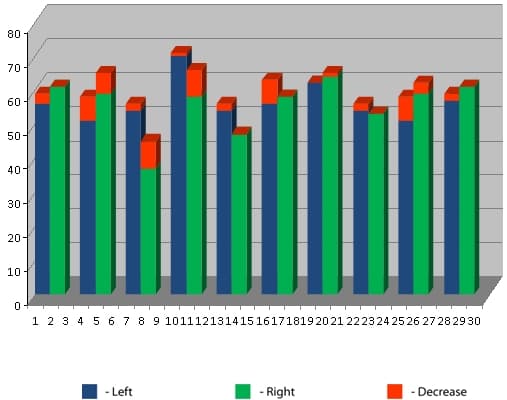

Effect of the Aires Defender based on electroencephalographic data.

We will now consider the affect of the Aires Defender on electroencephalograms (EEG) of the human cerebrum.

An electroencephalogram is a plot of a recording of the bioelectric activity of the cerebrum in the frequency range from 0.3 to 50 oscillations per second, divided into a number of bands (delta, theta, alpha, beta, gamma). An EEG can be used to evaluate processes occurring in the cerebrum and can be successfully employed in the diagnosis of various diseases and conditions of the central nervous system. The cerebral hemispheres generate radiation independently and may operate in concert or in an uncoordinated way. The cerebral hemispheres differ in their functions. The right hemisphere perceives intuitive, figurative, and abstract information, while the left hemisphere perceives concrete, logical information. For example, the center of speech is located in the left hemisphere. Human evolution is a result of both growth in the capacity of each hemisphere and an increase in the number and quality of interconnections between them. The number of inter-hemisphere connections is a manifestation of the coordination of the two hemispheres. A person is competent in all areas (physical, mental, social) only when the maximum number of interconnections between the hemispheres have developed in the brain and the interactions between them are harmonious and coordinated. The degree of coordination between the interconnections is marked by color in the charts: maximum coordination – pink, average – red, imbalance – dark blue, maximum imbalance – light blue.

We present examples of changes observed in EEG parameters during use of the Aires Defender. We note that in no case was there an worsening of the initial measurements. For convenience, the EEG being compared are placed next to each other. On the left is the initial data. One the right is the baseline of Aires Defender usage.

Figure 1 on the left presents the initial EEG of a 30-year-old test subject before use of the Aires Defender. Complaints were made about poor diligence at the computer due to rapid eye strain, and about a decreased concentration and reduced memory. The “flat” EEG clearly has low-amplitude alpha activity.

On the right is a second EEG, after using the Aires Defender for 30 days. There is a noticeable increase in the alpha rhythm. The test subject mentioned an increase in capacity to work and an improvement in concentration and memory.

It can be seen in Figure 2 that the initial EEG recorded destructive interaction (dark blue) in the delta-1 band and the depletion of intercenter links. After a month of using the Aires Defender, the destructive interactions were eliminated, and the intercenter links in the delta-1 band were restored and concentrated. Ideally, each center should have a coordinated, consonant link (pink or red) with all others, which would increase its functional capabilities and the abilities of the entire system as a whole.

based on cross-correlation in the delta-1 band.

based on cross-correlation in the delta-2 band.

It can be seen in Figure 3 that the initial EEG recorded destructive interaction (dark blue) and the depletion of intercenter links, also in the delta-2 band. After a month of using the Aires Defender, the destructive interactions were eliminated, and the intercenter links in the delta-2 band were restored and concentrated.

Fig. 4 – The depletion of intercenter links was observed in the initial EEG. After a month of using the Aires Defender, the intercenter links in the theta band were restored and concentrated.

based on cross-correlation in the theta band.

based on cross-correlation in the alpha band.

Fig. 5 also shows a depletion of intercenter links in the initial EEG. After a month of using the Aires Defender, the intercenter links in the alpha band were restored and concentrated.

Fig. 6 – Destructive interactions (dark blue) and the depletion of intercenter links were observed in the initial EEG. After a month of using the Aires Defender, the destructive interactions were eliminated, and the intercenter links in all frequency bands were restored and concentrated.

based on cross-correlation in all bands.

Figure 7 shows the phase delays (blue and dark blue) at the different leads before the application of the Aires Defender. This creates a functional asymmetry of the hemispheres. After application of the Aires Defender, symmetry is restored.

In summary, the EEG data presented indicates entirely positive changes in the functional state of the central nervous system with the use of the Aires Defender, in all examined cases.